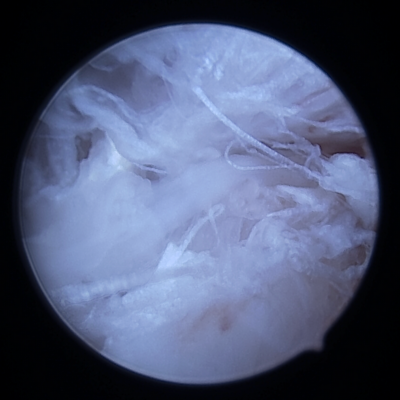

- Arthroscopie si nécessaire pour confirmer la rupture de ligaments croisés et d’éventuelles les lésions méniscales